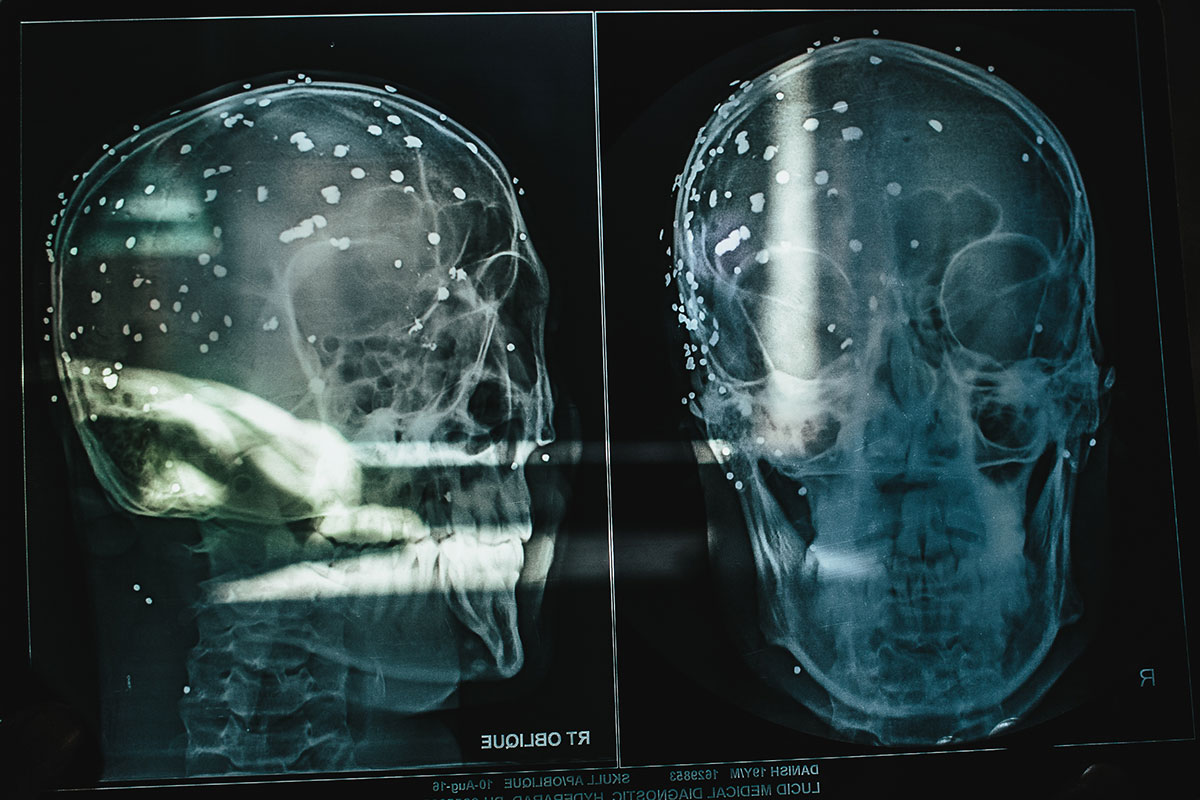

Blind in Kashmir with 100 pellets lodged in his head

The story of young Danish, who was shot by a pellet gun and suffered irreversible damage to his eyesight.

On the evening of July 17, 2016, after the curfew had been lifted, Danish was hit by pellets in his face and eyes from a distance of about 10 metres, as he sat chatting with his friends at a tea stall near his house. He felt sharp pain and fell down with the shock. His friend, Aashiq, tried to lift him up. This was the last image that Danish saw.

The pellet gun fires more than 500 sharp lead pellets at high velocity. Doctors say that even a single pellet entering the eye at that speed can cause grievous and irreversible damage.